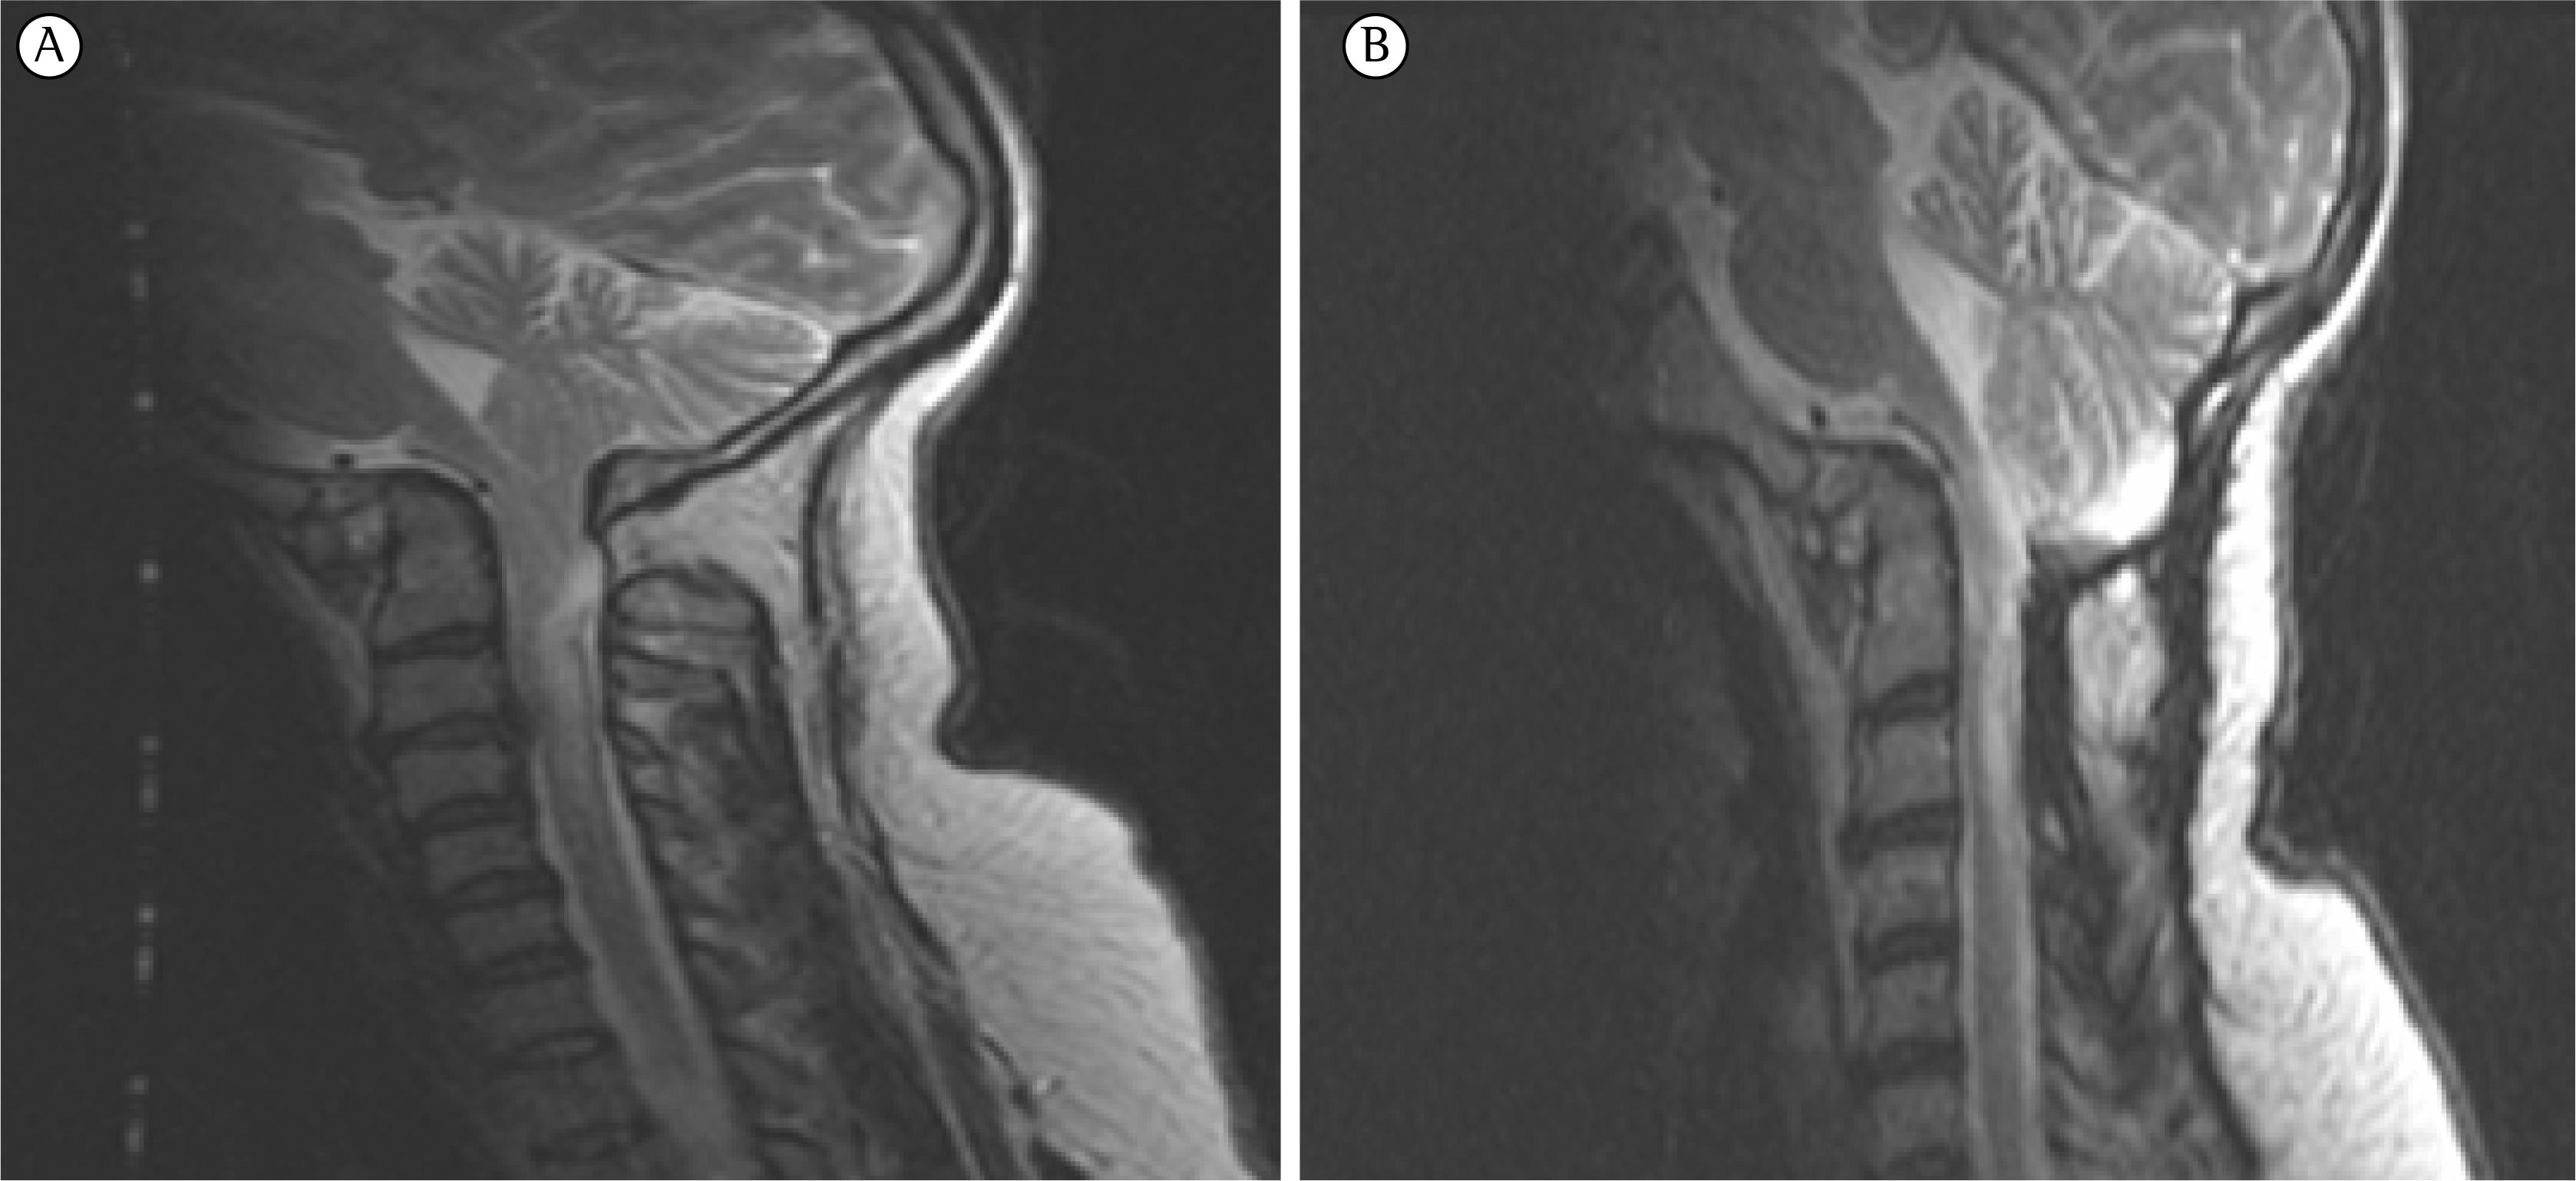

Chiari I malformation is the most common variant of the Chiari malformations and is characterized by a caudal descent of the cerebellar tonsils (and brainstem in its subtype, Chiari 1.5) through the foramen magnum. Symptoms are proportional to the degree of descent. MRI is the imaging modality of choice. Treatment with posterior decompression.

RM en secuencia T1. Malformación ArnoldChiari tipo 1. Herniación... Download Scientific Diagram

Malformación de Chiari tipo 1. RM cerebral, proyección lateral.... Download Scientific Diagram